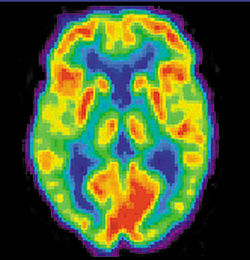

- Психофизиологические методы (ЭЭГ, ПЭТ)